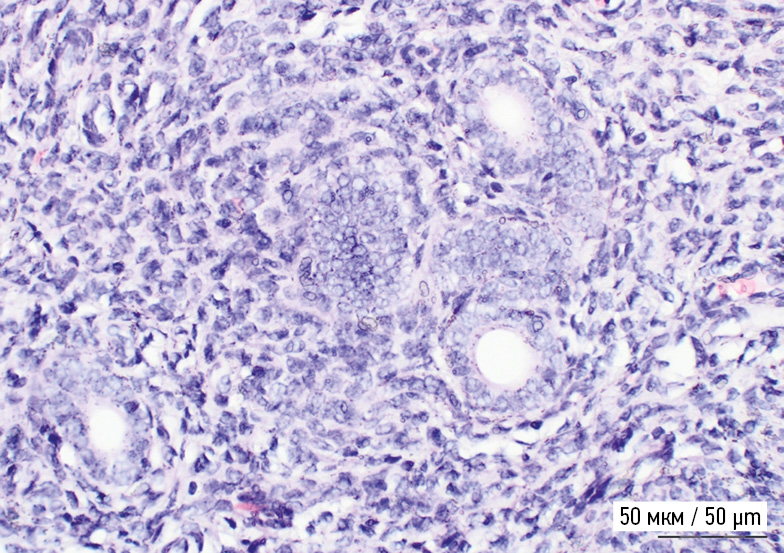

Таким образом, у 20 из 21 крысы гистологически верифицирован аденомиоз, что составило 95,2 % (рис. 4). По результатам морфологического исследования в мышечном слое визуализированы железы эндометрия, миометрий представлен переплетенными утолщенными полосами гладкомышечных клеток, перемежающимися со слоями коллагена.

Рис. 4. Гистологический препарат миометрия крысы. Железы аденомиоза в миометрии. Увеличение ×400

Fig. 4. Histological preparation of the rat myometrium. Adenomyosis glands in the myometrium. Zoom ×400

В контрольной группе животных (n = 5), выведенных в 90-й день постэмбрионального развития на основании результатов морфологического исследования визуализированы регулярные концентрические слои гладкомышечных клеток, отсутствие желез и стромы эндометрия в миометрии (рис. 5). Таким образом, в P90 у животных, получавших тамоксифен (n = 5), аденомиоз развивался в 100 % случаев, что отличалось от показателя в группе контроля (p = 0,0079). Морфологически аденомиоз характеризовало наличие желез эндометрия в миометрии, в отдельных случаях с небольшим количеством стромы эндометрия. Другой особенностью было нарушение концентрических и продольных полос гладких мышц миометрия: вместо регулярных концентрических слоев гладкомышечных клеток обнаружены переплетенные утолщенные полосы гладкомышечных клеток, перемежающиеся со слоями коллагена. Во многих из этих измененных зон наблюдали полиморфно-ядерные лейкоциты и эозинофилы, отсутствующие у животных контрольной группы.